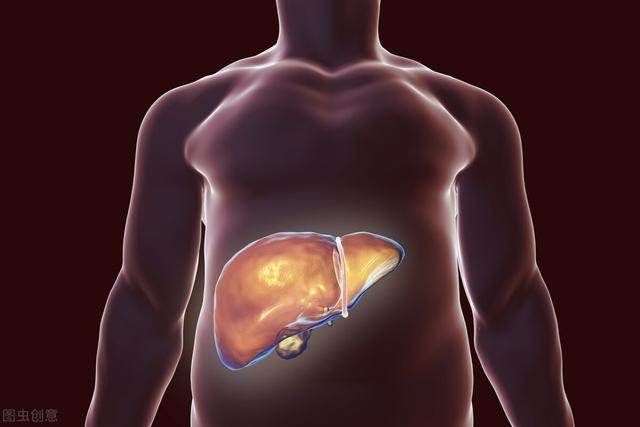

1.肝炎

B/C型肝炎、肝硬変、肝癌は、中国における肝癌発症の最も重要な3部作である。欧米先進国の肝臓がんは、アルコール性肝炎、肝硬変、肝臓がんが主な原因であり、原因は似ている。肝炎による肝細胞へのダメージがある程度蓄積されると、発がんのリスクが高くなる。

肝硬変→肝がん

中国では、肝炎→肝硬変→肝がんの3部作が存在する。海外で最も一般的なものはアルコール誘発性肝硬変。

もし肝硬変を基礎疾患とするB型肝炎の既往歴は、肝癌のハイリスク群である。画像所見で疑わしい部位やαフェトプロテインの上昇を伴う場合は、がんが存在する可能性がある。

一人だ、肝硬変が発症している場合は、超音波検査とAFP(α-フェトプロテイン)を定期的に見直す。

二、B型肝炎に罹患している場合は、積極的に治療すること。

三、喫煙と飲酒をやめる。

医学統計によると、中国の原発性肝臓癌の90%以上はHBsAg陽性のB型肝炎患者である。また、B型肝炎患者は定期的にアルファフェトプロテイン指数と肝臓超音波検査を再検査する必要があり、肝臓癌の早期発見の確率を高めることができる。

肝臓がんに変化する可能性のある疾患:

- ウイルス性肝炎

- 様々な原因による肝硬変

3.B型慢性肝炎:中国ではB型肝炎ウイルスキャリアは10%に達し、肝臓がんの80%はB型慢性肝炎が原因である。肝細胞癌は慢性B型肝炎と密接な関係があり、肝炎、肝硬変、肝細胞癌は肝臓三部作と呼ばれている。B型慢性肝炎の患者さんは、定期的に肝機能とB型肝炎ウイルスDNA定量を見直し、抗ウイルス薬を内服してウイルス価を正常にする必要があります。B型慢性肝炎のハイリスク・リスク背景とハイリスク・リスク年齢段階の人々にとって、早期肝がんの定期的なスクリーニングは、傷害保険に加入し、6ヵ月ごとにチェックすることと同じである。AFP+肝臓、胆嚢、脾臓B超これにより、少なくとも80%の肝臓がんを2-125px以内に検出することができる。

- 肝硬変は肝がんの前がん病変である。わが国が世界有数の肝がん大国であるのは、B型肝炎大国であることに由来する。B型慢性肝炎は最も危険な要因です。世界では毎年約60万人が新たに肝臓がんに罹患しており、その80%が中国で発生している。B型肝炎ウイルスに感染すると慢性肝炎になり、肝硬変、そして肝臓癌へと進行する。B型肝炎は肝炎→肝硬変→肝がんの "3ステップ "で肝がんに至る。

C型肝炎も同じ経路をたどって肝臓がんに発展する。

肝がんの初期症状と慢性肝炎を区別することは難しく、慢性肝炎から肝がんへの進行を防ぐには、慢性肝炎の積極的な治療に加えて、以下のことが必要である。肝臓癌の早期発見は、α-フェト蛋白の定期的な血液検査と超音波検査で可能である。

まず第一に、中国は肝炎の国であり、肝炎、肝硬変、肝臓癌の三部作は憂慮すべきものではないという医学界の噂は、肝炎の臨床経験が肝臓癌患者へと発展した少数派である。『ウイルス性肝炎患者は長生きすればするほど、いずれ肝臓癌になる』というのは少し絶対的に聞こえるが、確かに肝臓癌の最も重要な原因因子の一つである。したがって、ハイリスクグループは定期的に検診を受け、早期診断・早期治療を行うことが重要である。